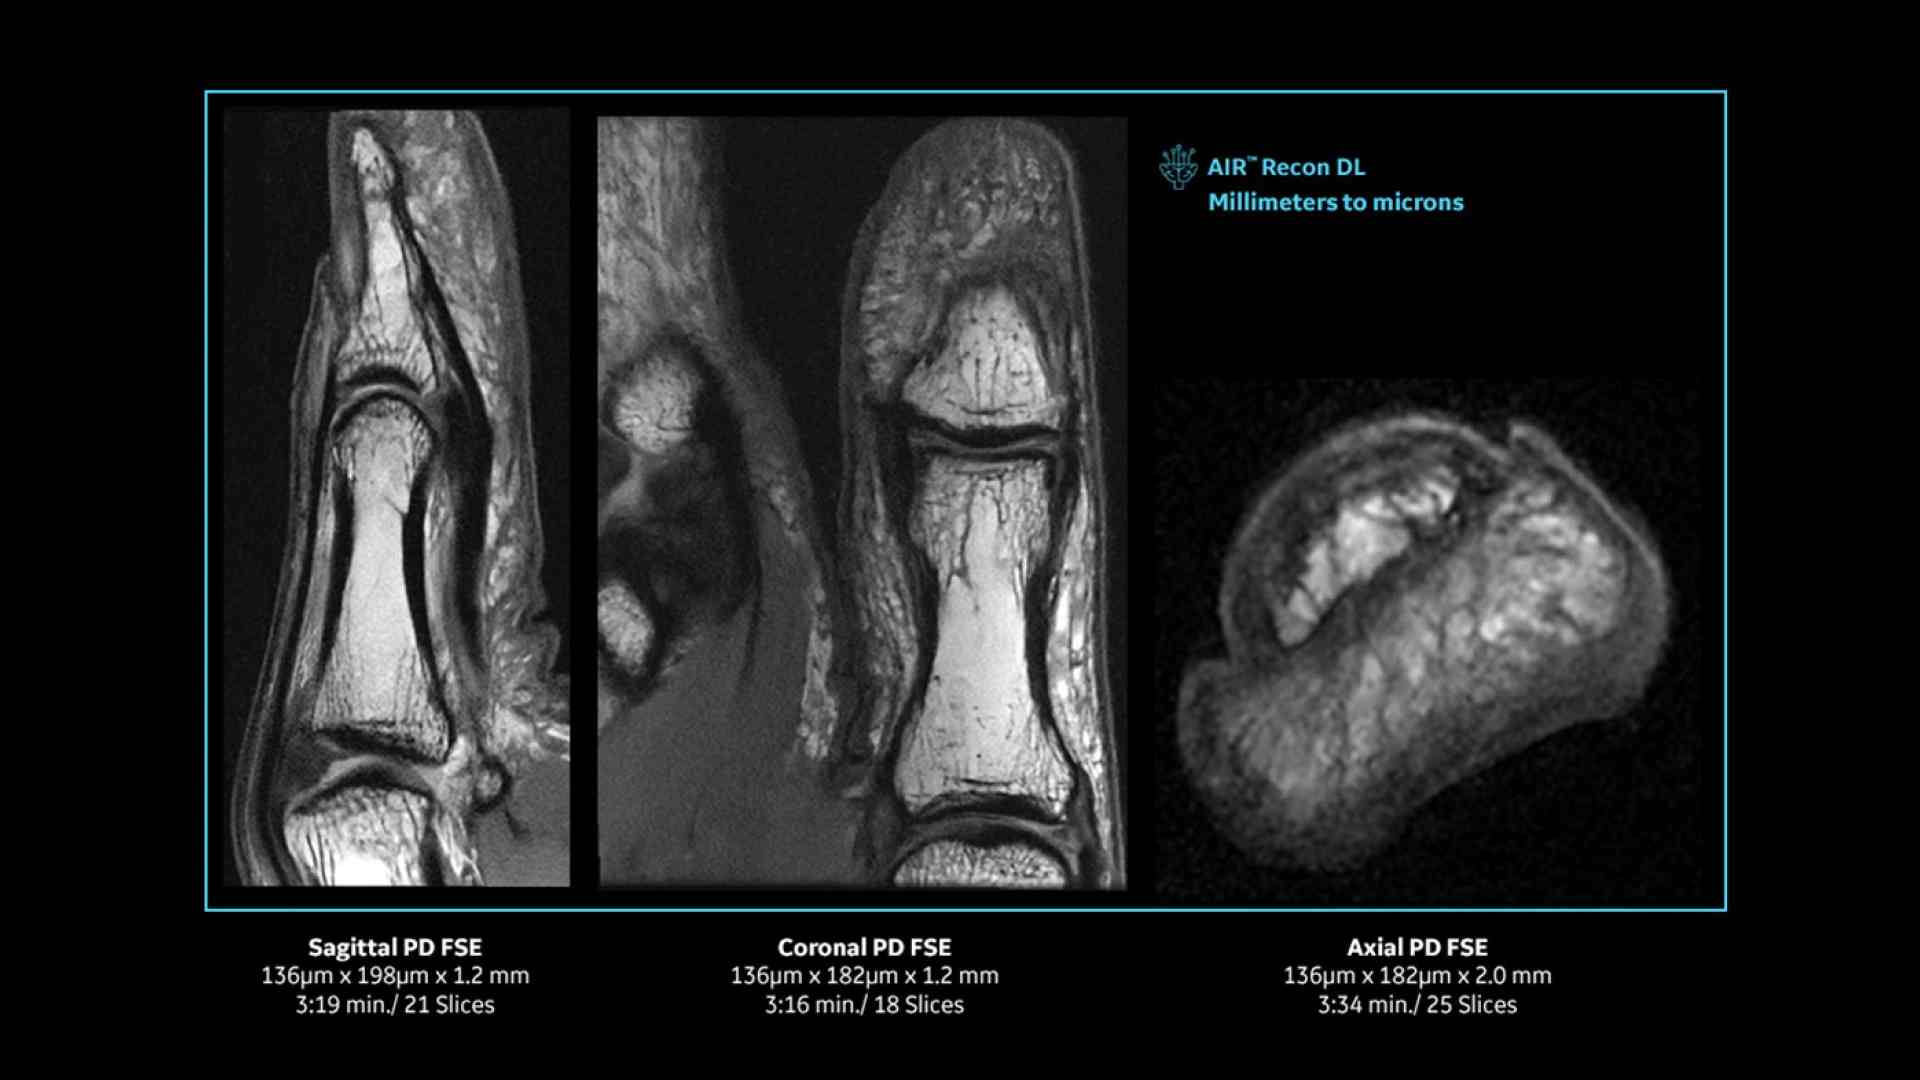

Revolutionary, deep-learning-based reconstruction techniques such as AIR™ Recon DL provide sharper, clearer, and accurate images

Pin-sharp image quality and exceptional speed with AIR Recon DL and Sonic DL​

Experience pin-sharp precision and remarkable speed with a 3T SIGNA Premier MRI scanner, coupled with AIR Recon DL and Sonic DL™.